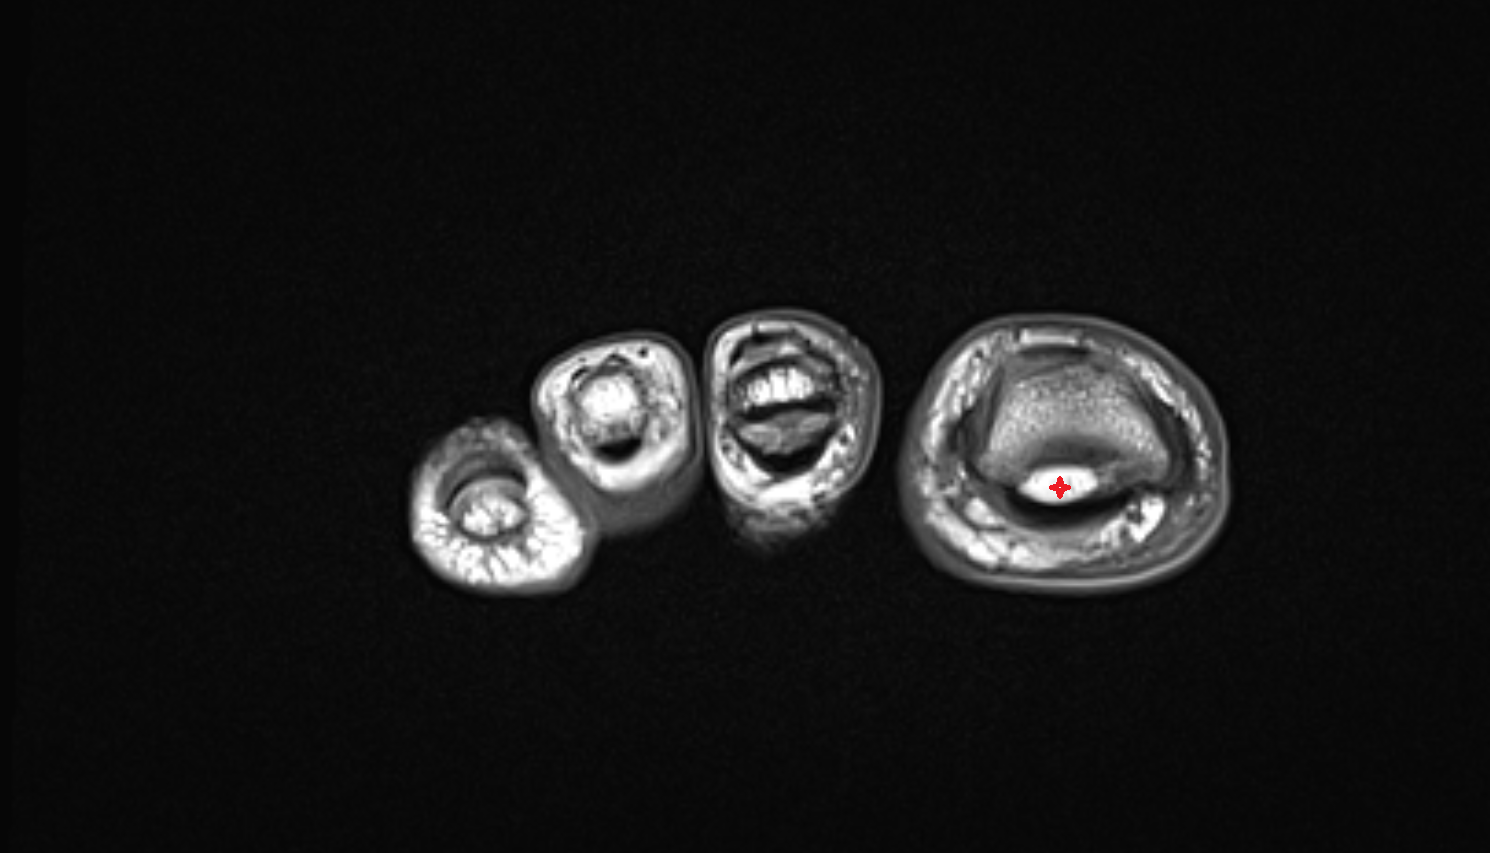

- Sesamoid bone of great toe

- Lateral sesamoid bone

- Medial sesamoid bone